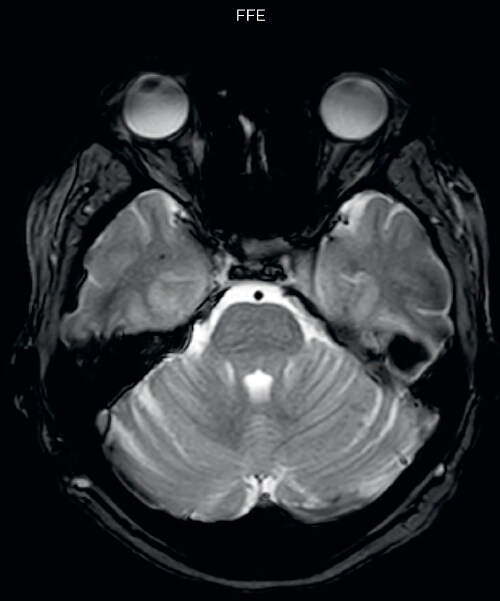

“We saw MultiVane XD provide remarkable improvement, not only for artifacts caused by patient motion, but also for the extent of pulsation artifacts in the basal cisterns. Based on these results, we have added the MultiVane XD sequence to our brain studies,” says Dr. Nickerson. “MultiVane XD is especially useful when imaging patients with diseases that cause white matter changes on T2-weighted images, such as MS, small vessel disease, vasculitis and sarcoidosis,” says Dr. Nickerson. “Many of these are only visible on T2-weighted or FLAIR images, and sometimes aren’t even seen with FLAIR images. However, when using MultiVane XD and we don’t see any motion on the rest of the scan, but still do see a signal abnormality, we can probably attribute that to a real disease process, rather than an artifact.”

The images made with MultiVane XD show significant reduction in motion artifact compared to the T2-weighted images without MultiVane below them. Scanned on Ingenia 3.0T